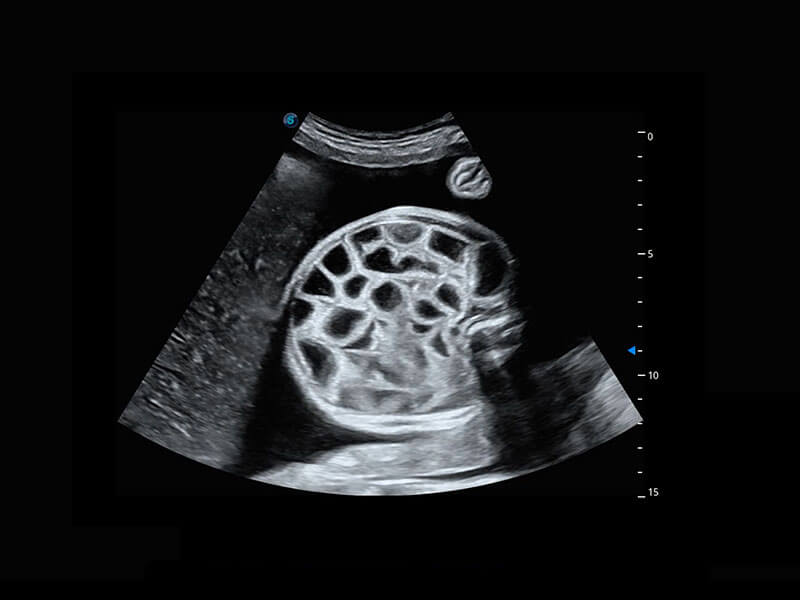

腔内妇科-宫腔分离

腔内妇科-卵巢

腔内三维-宫内节育器

腔内三维-光影成像

P60优异的图像质量搭载专科探头,在妇科基础疾病的诊断、卵泡生长的监测、输卵管通畅情况的判别等方面为您提供生殖应用方案。